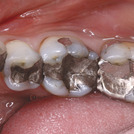

While monolithic restorations are simpler for labs to produce than layered restorations, they require much more from the selected material. And when monolithic restorations are completed without a model, the performance of the material must be even greater as any weak link in the workflow can create a compromised restoration. A successful model-free process requires a reliable material, a highly skilled technician, excellent software and an outstanding mill. Here’s my step-by-step technique for a recent case: